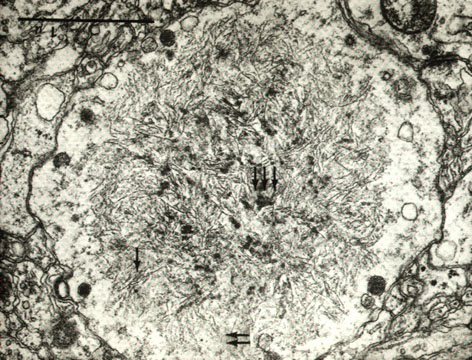

Fig 35 - Lafora body under

Electron microscopy.

Aggregates of randomly

Arranged fibrils

60A in diam.

(3)